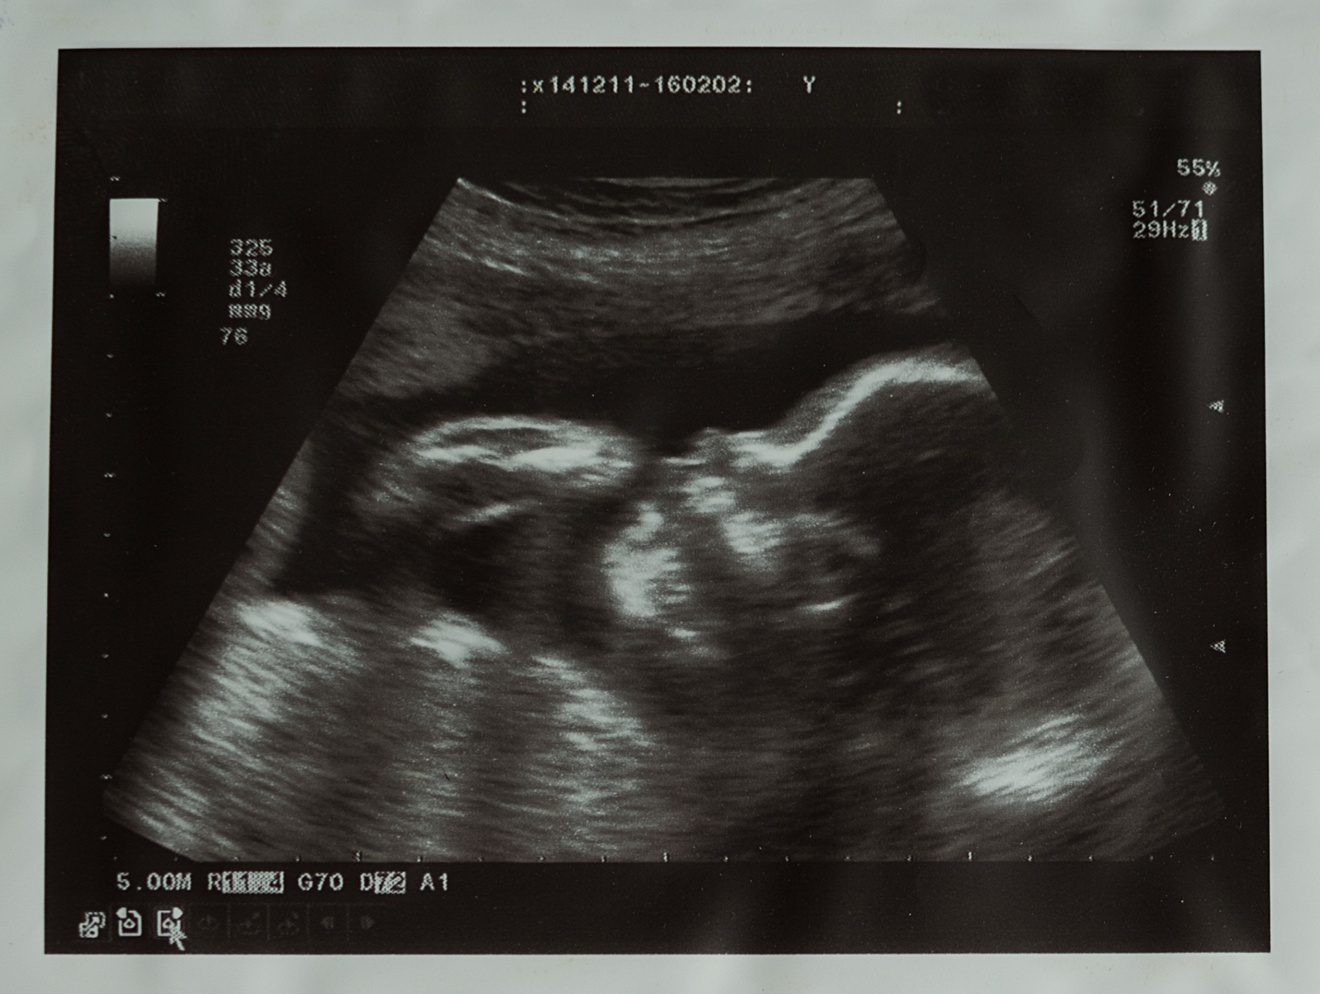

妊娠中、赤ちゃんの成長を感じる瞬間は何よりの喜びですが、従来の白黒のエコーでは、赤ちゃんの様子をなかなかイメージしづらいこともあります😅

4Dエコーは、3Dエコーに時間(動き)を加えた、胎児の様子をリアルタイムで動画として見ることができる技術です。従来の2Dエコーでは平面的な白黒の画像しか見られませんが、3Dエコーでは立体的な画像が得られます。4Dエコーはその3Dの画像に動きが加わることで、まるでお腹の中の赤ちゃんが動いているように感じることができます。

⬇️ 2D